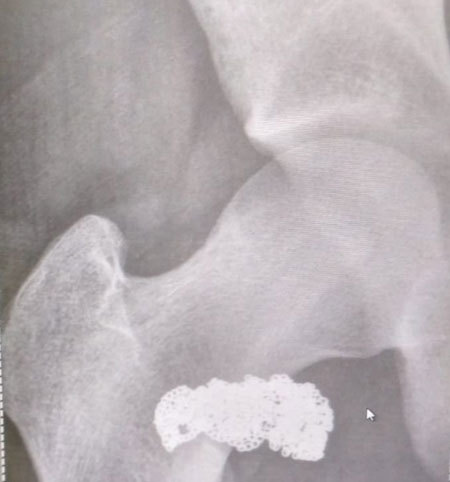

Ladrão engole cordão de ouro e é preso após raio-x Foto: Divulgação/PM

Um homem foi preso por roubar um cordão de ouro na Avenida Vieira Souto, em Ipanema, na Zona Sul do Rio, no sábado (20). Ele engoliu a joia e se disse inocente, mas foi preso depois que o exame de raio-x constatar que o cordão estava no abdômen dele. Segundo informações do 23º BPM (Leblon), o turista espanhol Eduardo Maese Alvarez disse à polícia que Yuri de Lima praticou o roubo e em seguida engoliu o cordão. A versão foi confirmada por testemunhas. O caso foi encaminhado para a 12ª DP (Copacabana). A polícia decidiu levar o autor do roubo para um exame na UPA de Copacabana onde a ressonância mostrou uma mancha, próxima do seu abdômen. Com o zoom, ficou claro que era o cordão. Em seguida, ele foi preso em flagrante e o cordão recuperado, segundo a PM.